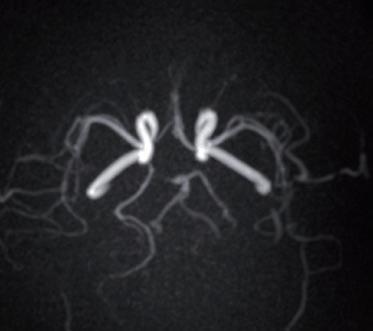

The Vantage Galan 3T / Saturn X Gradient has been installed as a research partnership and collaboration between GHUPPN, Canon Medical and Olea Medical. The partnership’s main objective is to support GHUPPN’s research project and improve understanding of MR’s contribution to NeuroImaging, and especially for mental-, neuro-vascular, neuro-oncology and epileptogenic networks.

GHUPPN will evaluate specific MR sequences for brain tumor and acquire a better understanding of the evolution of brain gliomas by deeply analyzing their spatial organization and get a better delineation between tumors and surrounding benign brain parenchyma. A second research priority is to develop and evaluate contribution of contrast-free MR angiography for head and neck vessels and compare to current gold-standard MR angiography with contrast-media injection. Leveraging its extensive expertise in Psychiatry, GHUPPN is also planning to use the Vantage Galan 3T/ Saturn X Gradient to evaluate the contribution of dedicated MR pulse sequences for children and teenagers with psychiatric disorders and cognitive development limitation.

The Vantage Galan 3T, with powerful gradients and highend RF coils technology, is the perfect device to support such research project and objectives. The wide range of advanced pulse sequences, including the latest innovation, such as Advanced intelligent Clear-IQ Engine (AiCE) and Compressed SPEEDER, provide the most efficient solutions to the researchers, while bringing outstanding image quality and resolution. Alongside scanning, advanced post-processing software for both qualitative and quantitative analysis is provided through Olea Medical solutions.

An increasing awareness of the potential risks associated with gadolinium-based contrast agents has revealed the need for alternative, contrast-free MR angiography techniques. Canon Medical offers a full range of non-contrast MRA sequences to minimize risk to patients with sensitivity to contrast while producing exceptional diagnostic images. Furthermore, free-breathing images can be acquired using Quick Star or k-t SPEEDER or using navigator-triggered sequences.